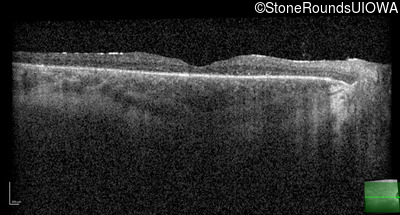

Optical Coherence Tomography - Right - 20/50

Exemplar / OCT Stack

OCT Stack